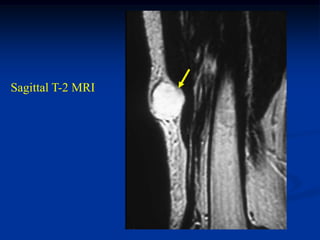

Case #251

11 year male with desmoid foot

Sagittal T-1 MRI

Axial T-1 MRI

Axial T-2 MRI